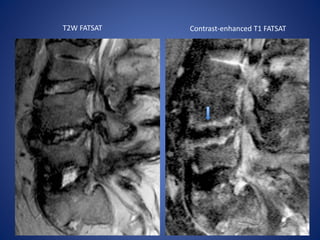

Pyogenic spondylodiskitis in a 54-year-old diabetic man.

T1W FATSAT T2W FATSAT

Contrast-enhanced T1-weighted fat-suppressed

Pyogenic Spondylodiskitis Classic imagingfindings include a narrowed disk space with destruction of the neighboring vertebral endplates. Spine infection usually begins in the anterior aspect of the vertebral body because of its rich blood supply and subsequently extends through the disk to neighboring vertebral bodies. MRI shows decreased T1 signal intensity and increased T2 signal intensity in the affected vertebral endplates and disk. Post contrast images at an early stage of the disease process include enhancement of the disk and along the vertebral endplates; at a later stage, enhancement is accompanied by progressive destruction of the vertebral body.

Pyogenic spondylodiskitis ina 54-year-old diabetic man. T1W FATSAT T2W FATSAT

• #36 (a, b) Sagittal T1-weighted (a) and T2-weighted fat-suppressed (b) MR images demonstrate endplate-centered bone marrow edema with high signal intensity in the disk (arrowhead in b).

• #37 …..enhancement in the disk. Percutaneous aspiration of the disk contents yielded S aureus.